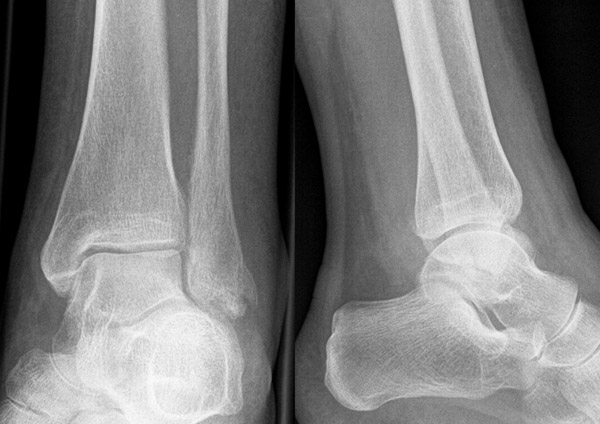

Die Standard-Röntgenaufnahmen des oberen Sprunggelenks bestehen aus drei Aufnahmen: der antero-posterioren Aufnahme (ap), der antero-posterioren Aufnahme mit Innenrotation des Unterschenkels von 20° („Mortise view“), sowie der streng seitlichen Aufnahme (siehe S2-Leitlinie Sprunggelenksfraktur). In der Röntgen-Bildgebung sollte neben den klassischen Frakturzeichen die Integrität der Syndesmose beurteilt werden. Dies erfolgt über die Beurteilung der Breite des lateralen und medialen Gelenkspalts („medial clear space“), des tibiofibularen Abstands 1cm oberhalb des OSG-Gelenkspalts („tibiofibular clear space“), bzw. der tibiofibularen Überlappung. Eine Verbreiterung des tibiofibularen Abstands über 5 mm oder die Erweiterung des medialen Gelenkspalts können Zeichen einer begleitenden Syndesmosenverletzung sein. (Abbildung 3) 6.

Liegt eine Fraktur des oberen Sprunggelenks vor, ist sowohl zur Entscheidung für ein konservatives oder operatives Vorgehen, als auch zur Operationsplanung, ein ausreichendes Verständnis der Fraktur und ihrer Morphologie notwendig. Insbesondere bei komplexen Verletzungen ist dafür die konventionelle Röntgenaufnahme in vielen Fällen nicht ausreichend. So konnten z.B. Black et al. zeigen, dass die operative Strategie zur Versorgung von OSG-Frakturen in 24% basierend auf einer zusätzlichen CT-Bildgebung relevant geändert wurden 7. Dies betraf die Lagerung, die Wahl des Zuganges und die Art der osteosynthetischen Versorgung. Besonders häufig änderte sich das Vorgehen bei Verletzungen des medialen (21%) und des posterioren Malleolus (15%). Darüber hinaus führten dislozierte (dislozierte Frakturen 31% vs. nicht-dislozierte Frakturen 20%) oder komplexe Frakturen (Trimalleolar-Frakturen 29% vs. Unimalleolar-Frakturen 10%) besonders häufig zu relevanten Änderungen des operativen Vorgehens. Die Computertomographie ist daher, insbesondere bei Bi- und Trimalleolar-Frakturen, essentiell für das Verständnis der Fraktur und somit für die Planung und Durchführung der Operation. In Abbildung 4 und 5 sind exemplarisch ein Röntgen- und ein CT Befund gegenübergestellt.